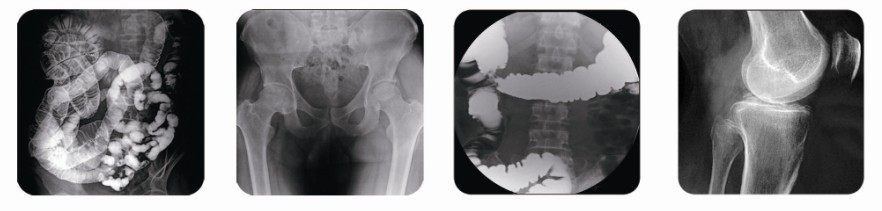

人類文明擁有著5000多年的發展歷史。同樣,醫學上對人體的臨床檢查也可分為多個階段,從最初的熒光透視、膠片成像,到影增、CCD技術,再到CR,都是在朝著一步一步科學嚴謹的方向發展。然而胃腸機的誕生可謂是跨時代的結晶,它的出現象征著人類臨床檢查邁向智能直接數字化的領域。

(普朗醫療品牌——高頻數字化醫用診斷X射線機PLD6800(800毫安腸胃機))